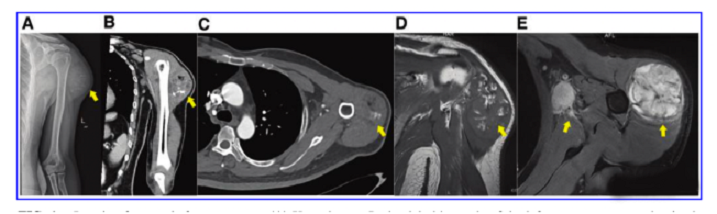

接受iPS細胞治療患者的畸胎瘤。(A) 在左上臂的三角肌中,觀察到一個圓形的混合密度腫塊,邊界不清,為9.6±5.2cm。(B) CT冠狀掃描顯示三角肌內有一圓形混合密度腫塊,邊界不清。(C)增強CT軸向掃描顯示不均勻和中度強化。(D)MRI T1W以等信號為主,有不規(guī)則的高低信號區(qū)。(E) T2W也顯示高信號和斑片狀低信號區(qū),左腋窩有多個淋巴結腫大。

文中展示了該未成熟畸胎瘤的臨床,放射學和病理學特征,作者認為這種腫瘤不同于典型的未成熟畸胎瘤,特點是快速增長和局部淋巴結轉移,該新生腫瘤對典型化療方案沒有反應,磁共振成像顯示腫瘤的不均勻強化和豐富的血供。